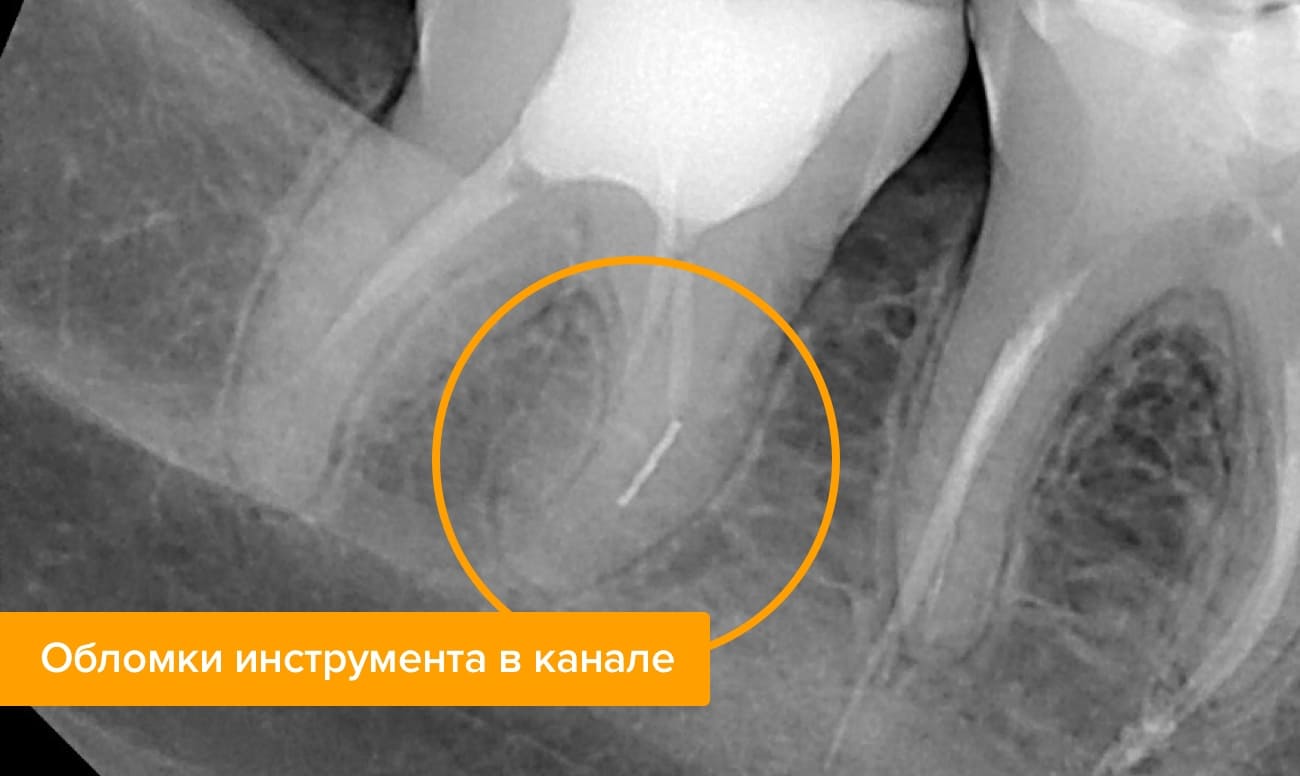

Конец стоматологического инструмента обломился и остался в канале

Такое тоже случается. Для извлечения пульпы и обработки каналов используются очень тонкие инструменты, которые требуют от врача высокой точности действий. Если манипуляции производятся с избыточным давлением на инструмент, без использования специального геля для смазки или просто неаккуратно, то тонкий конец эндодонтического инструмента может отломиться и остаться в корневом канале. Тогда будет перекрыт доступ в канал, и станут невозможны его качественная обработка и пломбирование. Со временем это обязательно приведет к воспалению, болям и разрушению корня зуба.

Остаток металлического инструмента в канале корня

Во время удаления нерва, врач обязательно чистит каналы, используя для этого стоматологические инструменты. В ходе неумелой работы доктора обломок инструмента может остаться в одной из частей канал, хорошо, если в первой трети – тогда его можно будет легко извлечь.

Если же кусочек застрял под пломбой у самого основания корня – вытащить его будет не так просто. Стоматолог обязан сделать рентгеновский снимок, для подтверждения своей ошибки, раскрыть каналы заново и удалить часть инструмента. Иначе зуб нельзя будет полноценно запломбировать, а внутри в пустотах начнется активное размножение бактерий, разрушающих моляр.